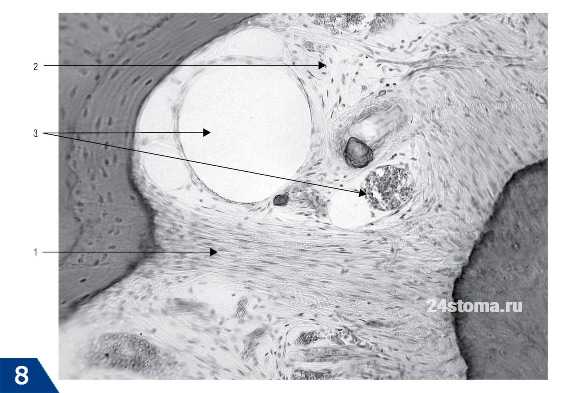

Существует 3 варианта соединения цемента и эмали зуба. Оно может быть либо «стык в стык», либо цемент может немного заходить на эмаль, либо может присутствовать полоска обнаженного дентина (рис.8). Исследования показали, что эмаль и цемент граничат «стык в стык» - только в 30% случаев. При этом 60% зубов имеют наслоение цемента на край зубной эмали (рис.9), а полоска обнаженного дентина встречается в 10% случаев.

Рис.8, где 1 - эмаль, 2 - дентин, 3 - цемент, и варианты соединения эмали и цемента (I - цемент частично заходит на зубную эмаль; II - цемент стыкуется с эмалью, III - цемент не доходит до эмали зуба).